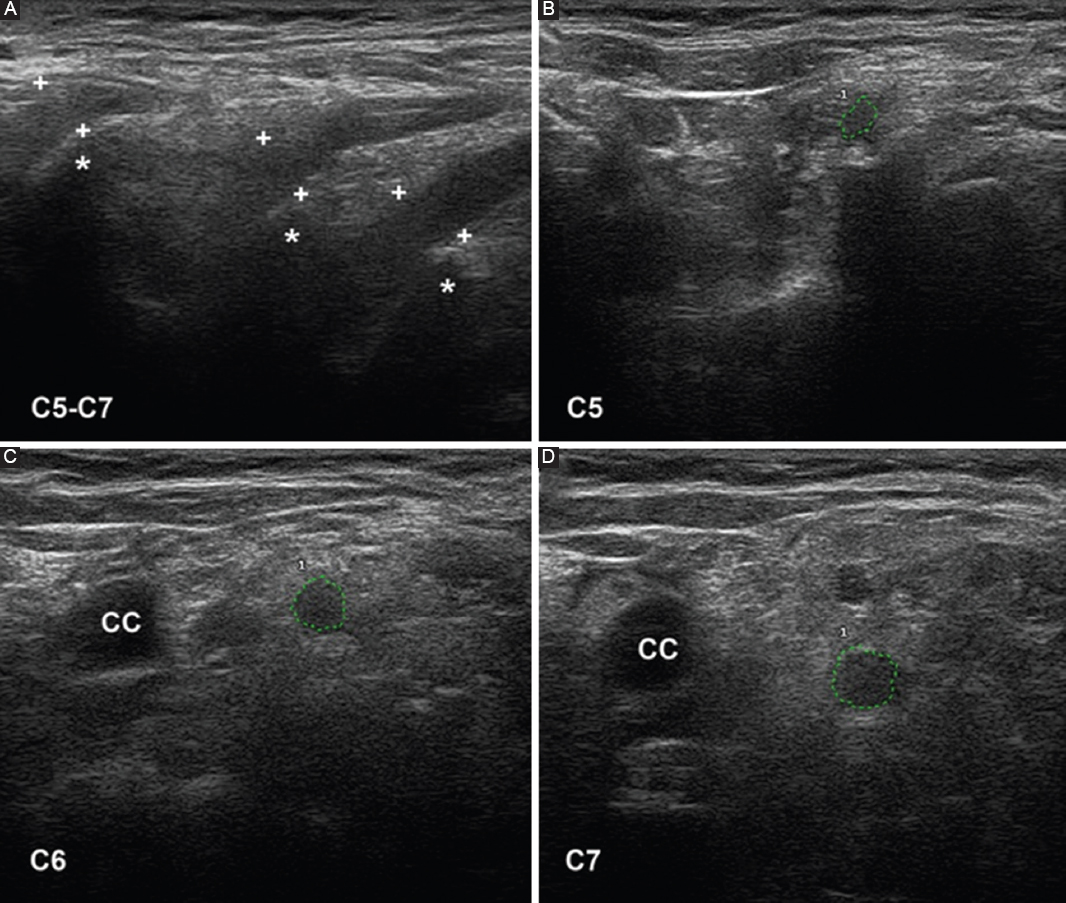

Ultrasonography is a useful diagnostic technique for studying PNS pathology57. With colleagues I have conducted an ultrasonography study in six consecutive patients with early and severe GBS, four categorized as AIDP and two as AMSAN14. The outstanding sonographic alterations were located in ventral rami of C5-C7 nerves, and consisted of significant increase of cross-sectional areas, blurring of the epineurial hyperechoic rim or both (Fig. 7). In a fatal case of AIDP, there was an excellent correlation between sonographic and histopathological studies (Figs. 14 in Gallardo et al.14). Furthermore, a striking difference in the degree of pathology was observed between lumbar roots, lumbar spinal ganglia, ventral rami of lumbar nerves, and more distant nerve trunks (Fig. 2). These findings again confirm that inflammatory edema of the spinal nerves is a hotspot in early stages of GBS11,12 (Figs. 2 and 3). Our ultrasound findings in the cervical nerves have been confirmed in other studies5861, though there were discrepancies regarding the frequency of alterations in more distant nerve trunks. Considering that sonography results depend on the skill of the clinician performing the study, there is a great need for new prospective studies with international consensus62.

Figure 7. Ultrasound study of the ventral rami of nerves C5-C7, obtained on the 5th day of progression in a patient with fulminant acute inflammatory demyelinating polyneuropathy (same patient as in figures 2 and 3). A: sagittal images showing disappearance of the epineurial hyperechoic rims (crosses indicate calipers; asterisks indicate the transverse processes). B-D: short-axis ultrasound of the three cervical nerves, whose perimeters are marked with green dotted lines; their cross-sectional areas are abnormally large. Note the disappearance of the epineurial rims. CC: common carotid artery. Taken from Gallardo et al.14.